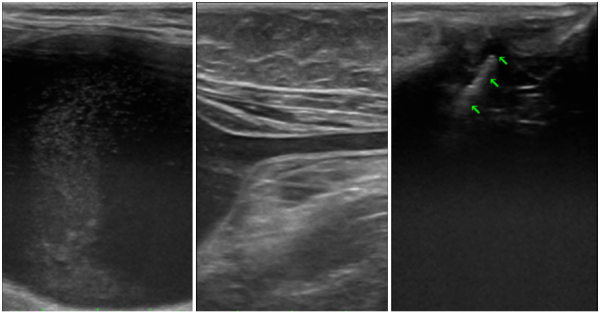

요도루성형술을 함께 진행한 이유

검사 과정에서 요관 문제 뿐만 아니라

요도 폐색 소견도 함께 확인되었습니다.

초음파 검사에서 방광의 심한 팽만과 함께 요도가 전반적으로 확장되어 있고,

요도 원위부 내 다량의 사결석과 결석이 관찰되었습니다.

└ 이러한 이유로 SUB 시술과 동시에

요도루성형술을 함께 진행했습니다.